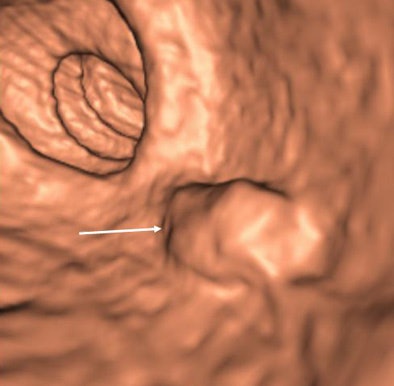

| Three views of a flat lesion: 60-year-old man with an 11-mm tubular adenoma seen at 2D (top) and 3D (below) VC, but initially missed at endoscopy (bottom). All images courtesy of Dr. Michael Macari. |

Segmental unblinded colonoscopy showed a total of six patients with seven polyps 10 mm or larger, including pedunculated (n = 1), sessile (n = 2), and flat (n = 4). Sensitivity was 43% (3/7) for VC with tagging, 86% (6/7) for VC with full bowel prep and 71% (5/7) for first-pass optical colonoscopy, the authors reported.

Three of four lesions missed with tagging had flat morphology. There were no significant differences (p > 0.12) among the three modalities with respect to sensitivity for detecting polyps 10 mm or larger.

"In the tagged lesions, three of the four missed lesions (at VC) were, in fact, flat," Macari said. The remaining flat lesion went undetected in 2D VC, "but during 3D review I noticed this flat lesion and it was confirmed at (optical colonoscopy)," he said. "So that means 3D is really helpful."